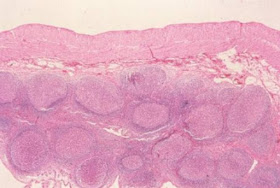

Figura

8- Material de biópsia do intestino delgado, em microscopia óptica comum,

grande aumento, mostrando a presença de trofozoitas de Giardia na luz do

intestino próximos a uma vilosidade (seta).